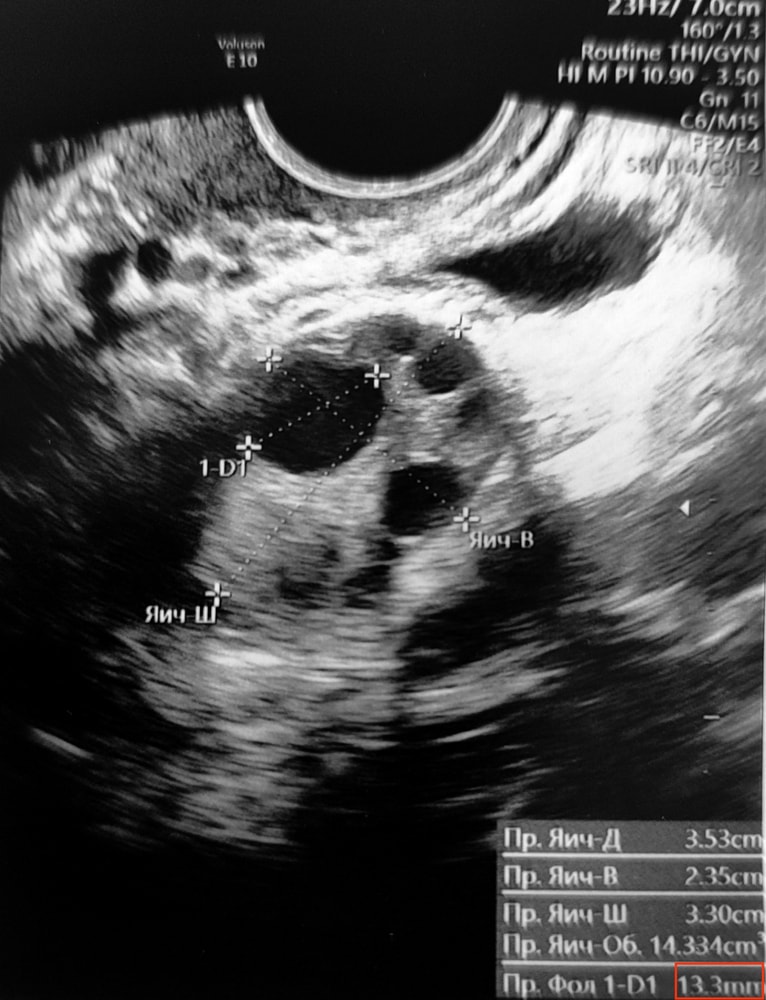

Планирование беременностиОчень неожиданно что пик ЛГ пришелся на 12 ДЦ. Потому что на 9 ДЦ на фолликулометрии Фолликул был 11-13 мм (точно не поняла, по заключению УЗИ 11мм по фото УЗИ 13мм). Я думала дню к 15 дорастет и тест вчера вечером был такой бледный. Получается примерно завтра будет овуляция, а ПА был вчера вечером, даже не знаю нужно как-то ещё сегодня уложиться🤔🤔 или лучше тогда завтра. Вроде каждый день тоже не полезно для сперматозоидов. Гинеколог говорила ПА раз в 2/3 дня.